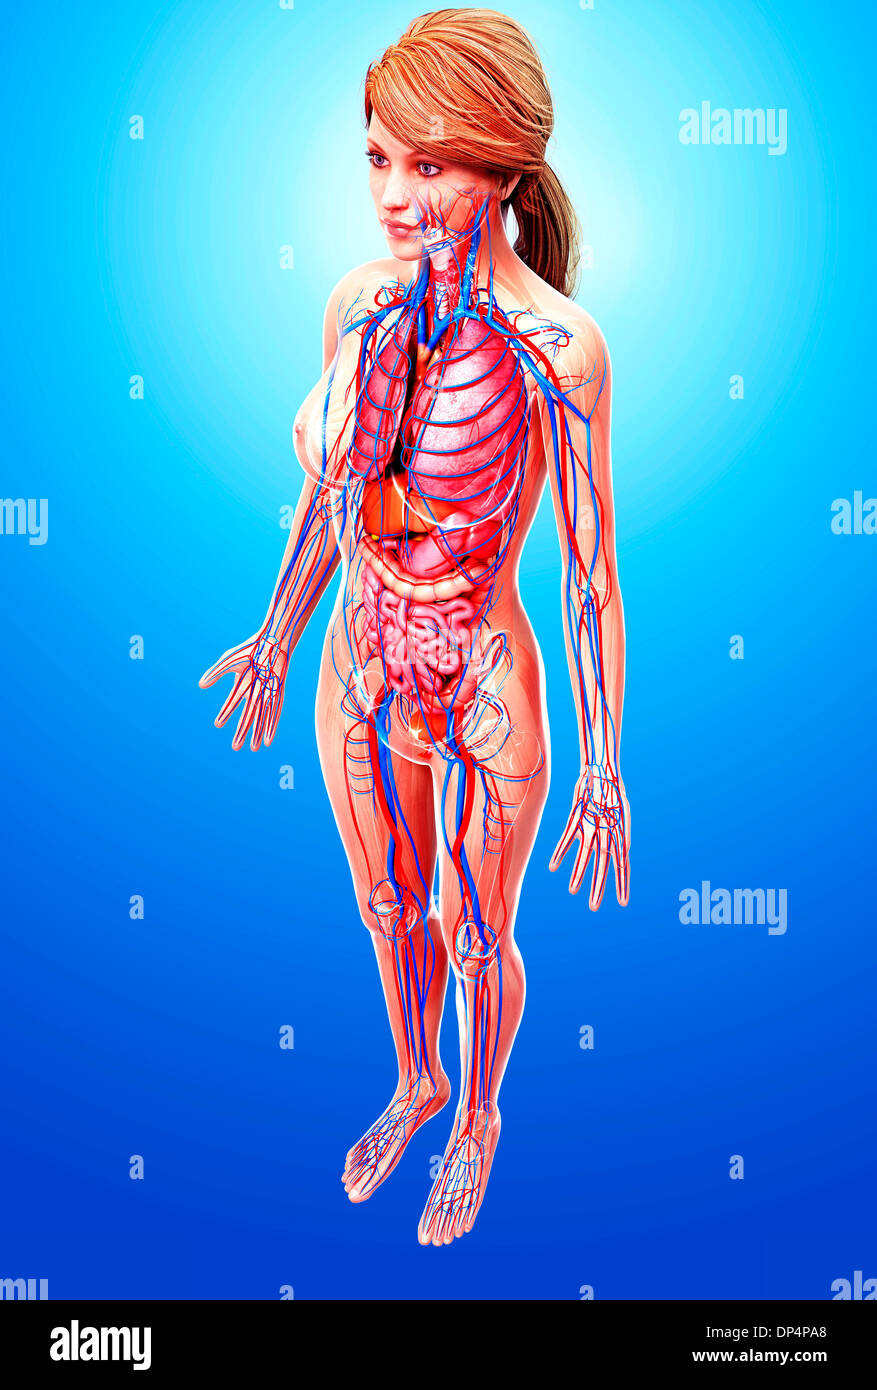

female anatomy art Complete female anatomy 3d model

fineartamerica.comFemale Anatomy, Artwork Stock Photo - Alamy

fineartamerica.comFemale Anatomy, Artwork Stock Photo - Alamy

fineartamerica.comFemale Anatomy, Artwork Stock Photo - Alamy

fineartamerica.comFemale Anatomy, Artwork Stock Photo - Alamy

www.alamy.comFemale Anatomy, Artwork Stock Photo - Alamy

www.alamy.comFemale Anatomy, Artwork Stock Photo - Alamy

bocadowasubo.github.ioFemale Anatomy, Artwork Stock Photo - Alamy

bocadowasubo.github.ioFemale Anatomy, Artwork Stock Photo - Alamy

fineartamerica.comFemale Anatomy, Artwork Stock Photo - Alamy

fineartamerica.comFemale Anatomy, Artwork Stock Photo - Alamy

www.etsy.comFemale Anatomy, Artwork Stock Photo - Alamy

www.etsy.comFemale Anatomy, Artwork Stock Photo - Alamy

www.alamy.comFemale Anatomy, Artwork Stock Photo - Alamy

www.alamy.comFemale Anatomy, Artwork Stock Photo - Alamy

www.alamy.comFemale Anatomy, Artwork Stock Photo - Alamy

www.alamy.comFemale Anatomy, Artwork Stock Photo - Alamy

fineartamerica.comFemale Anatomy, Artwork Stock Photo - Alamy

fineartamerica.comFemale Anatomy, Artwork Stock Photo - Alamy

Female Anatomy, Artwork Stock Photo - Alamy

www.alamy.comFemale Anatomy, Artwork Stock Photo - Alamy

www.alamy.comFemale Anatomy, Artwork Stock Photo - Alamy

www.etsy.comFemale Anatomy, Artwork Stock Photo - Alamy

www.etsy.comFemale Anatomy, Artwork Stock Photo - Alamy

www.alamy.comFemale Anatomy, Artwork Stock Photo - Alamy

www.alamy.comFemale Anatomy, Artwork Stock Photo - Alamy

www.alamy.comFemale Anatomy, Artwork Stock Photo - Alamy

www.alamy.comFemale Anatomy, Artwork Stock Photo - Alamy

Female Anatomy, Artwork Stock Photo - Alamy

www.alamy.com3d Rendered Illustration Of The Female Anatomy Stock Photo - Alamy

www.alamy.com3d Rendered Illustration Of The Female Anatomy Stock Photo - Alamy

fineartamerica.com3d Rendered Illustration Of The Female Anatomy Stock Photo - Alamy

fineartamerica.com3d Rendered Illustration Of The Female Anatomy Stock Photo - Alamy

pixels.comFemale Anatomy, Artwork Stock Photo - Alamy

pixels.comFemale Anatomy, Artwork Stock Photo - Alamy

www.alamy.comFemale anatomy art print women body torso drawing illustration modern. Female anatomy photograph by pixologicstudio/science photo library. Female anatomy, artwork stock photo

www.alamy.comFemale anatomy art print women body torso drawing illustration modern. Female anatomy photograph by pixologicstudio/science photo library. Female anatomy, artwork stock photo